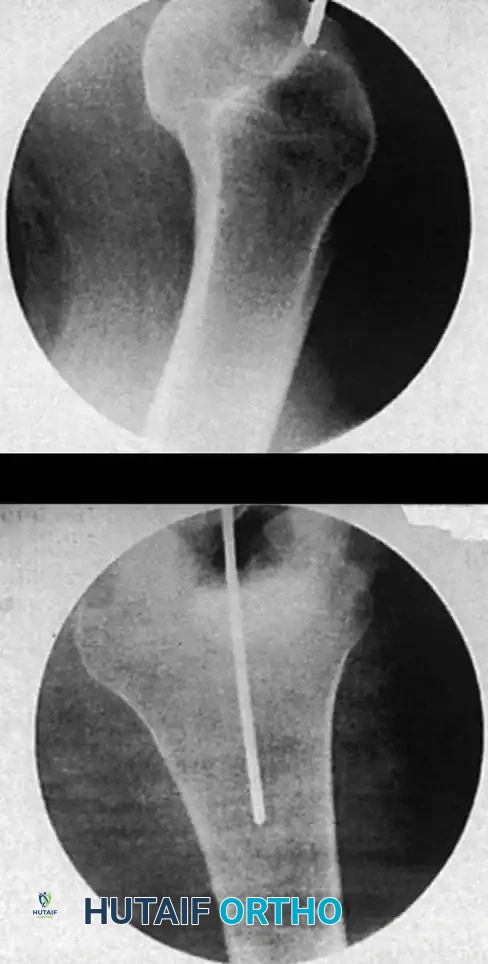

Entry Point and Guide Wire Placement

The choice of entry point—piriformis fossa versus greater trochanter—depends on the specific nail design.

3. Insert a guide pin or awl. For a piriformis entry, the starting point is in the piriformis fossa, slightly posterior to the central axis of the femoral neck on the lateral view.

4. Pass a ball-tipped guide wire down the proximal fragment, across the reduced fracture site, and into the distal metaphysis, centering it in the intercondylar notch.